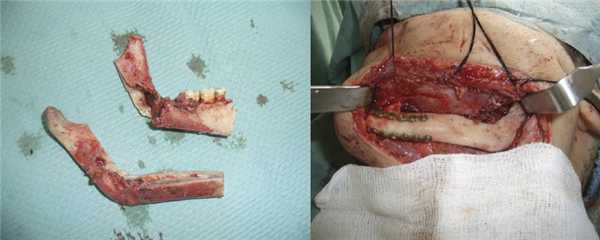

Кровотечения после эмболизации не было. Через 5 дней после эндоваскулярного вмешательства проведена операция резекции нижней челюсти слева с экзартикуляцией. При обнажении нижнего края челюсти выявлено множество нефункционирующих, запустевших сосудов артериального и венозного типов. Поверхность наружной кортикальной пластинки тела и ветви челюсти узурирована и не кровоточит. При скелетировании внутренней поверхности ветви нижней челюсти визуализирован обширный очаг деструкции кортикальной пластинки. В крылочелюстном и окологлоточном пространстве обнаружены гипертрофированные запустевшие сосуды, преимущественно венозного типа, в просвете которых находился Onyx 18 в виде рыхлой губки серо-черного цвета. За пределами операционной раны резецирован альвеолярный отросток вместе с зубами и была удалена губчатая кость и элементы сосудисто-нервного пучка. Из макропрепарата смоделирован ортотопический аутотрансплантат, проведена его реплантация с фиксацией титановыми пластинами к основному фрагменту нижней челюсти. Кровопотеря во время операции не превысила 200 мл (рис. 4). Рис. 4. Формирование реплантата из резецированного фрагмента тела и ветви нижней челюсти и его фиксация титановыми пластинами.